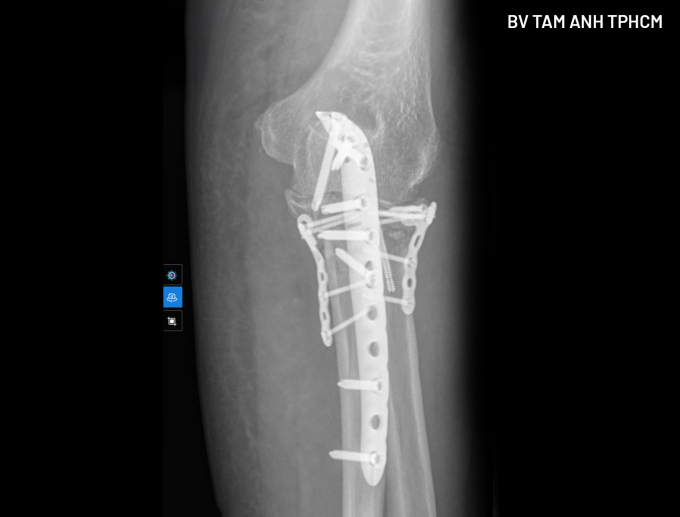

Để an toàn cho ca mổ, bác sĩ điều trị nội khoa cho bà Lợi trong 5 ngày, ổn định các chỉ số. Khi phẫu thuật, bác sĩ tiếp cận ổ gãy chỉ bằng một đường mổ duy nhất, từ phía sau, nắn chỉnh cả xương quay và xương trụ (mỏm khuỷu phía sau và mỏm vẹt phía trước) về đúng vị trí, sử dụng vít và nẹp để cố định, phục hồi giải phẫu hoàn toàn. Phương pháp này giúp giảm tối đa mất máu và tổn thương thần kinh mạch máu, các mô mềm khác. Người bệnh phục hồi nhanh hơn và giảm nguy cơ xảy ra biến chứng.